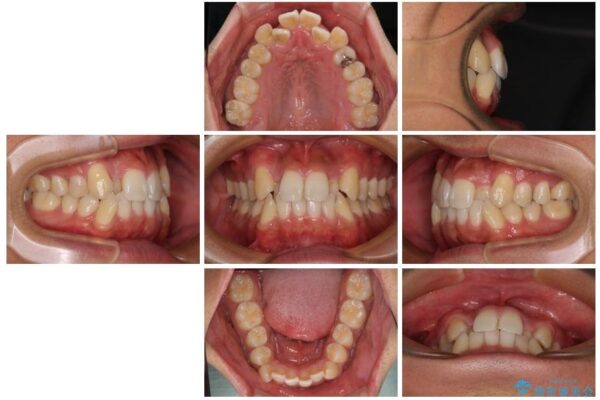

「八重歯を治したい」とご相談いただいた患者様の症例をご紹介します。

上下の前歯部に強い叢生(ガタガタの歯並び)があり、そのまま歯を並べると出っ歯になってしまう可能性がありました。

そこで、上下左右の第一小臼歯を抜歯し、歯が並ぶためのスペースを確保し叢生を解消する治療計画を立てました。

矯正装置は、審美性と費用面のバランスを考慮して、プラスチックブラケットとメタルワイヤーを使用しました。

透明感のあるブラケットを用いたため、従来の金属装置よりも目立ちにくく、日常生活での見た目の不安も軽減できます。

治療前

• 八重歯と前歯のガタガタを抜歯矯正で治療|クリアブラケット使用例 治療前画像